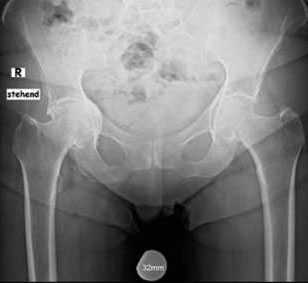

Пациент П. 64 лет на протяжении 3 лет отмечает выраженные, постепенно прогрессирующие боли в области правого тазобедренного сустава. Обратился в К+31 в мае 2017, осмотрен ортопедом, выполнены рентгенограммы тазобедренных суставов. Диагностирован коксартроз справа 3 ст, слева 2 ст. Рекомендовано оперативное лечение - тотальное эндопротезирование правого тазобедренного сустава.

Учитывая возраст пациента решено использовать протез бесцементной фиксации фирмы Zimmer, пара трения керамика\керамика.

Произведено предоперационное планирование, рассчётные размеры: ножка Avenir 6, чаша Trilogy 60, керамический вкладыш с внутренним диаметром 40 мм, керамическая головка 40 мм.